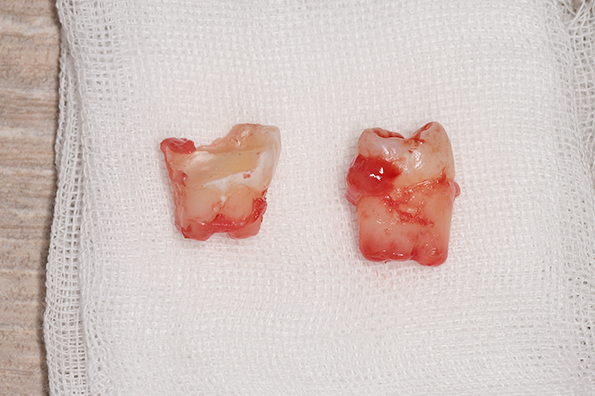

CASE 1

基本情報

| 年齢・性別 | 30代・女性 |

| 主訴 | 左右に分けて親知らずを抜きたい、できれば痛くなく抜きたい |

| 親知らずのはえ方 | 完全に出ていてまっすぐはえている |

| 抜歯期間 | 15分 |

| 抜歯費用 | 約2,000円(保険内) |

| 抜歯内容 |

何度か虫歯になり痛みはないが早めに抜きたい。 完全に頭が出ているため歯ぐきを切ったり骨を削らずに抜歯しました。 根の形も単純なため抜歯自体は5分もかからず上下ともに終わりました。 術後痛みや腫れも出ていません。 抜歯後は感染をしやすいため必ず抗生物質を飲み切ってください。 |